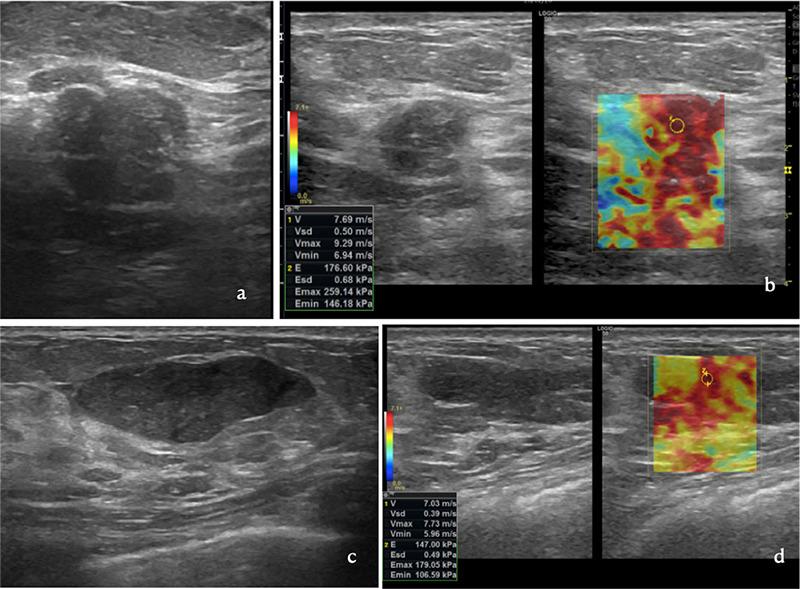

Simple fibroadenomas (SFAs), complex fibroadenomas (CFAs), and cellular fibroadenomas (CeFAs) are variants of fibroadenomas. Additionally, some degenerative, hyperplastic, and metaplastic changes may occur in fibroadenomas, forming complicated fibroadenomas. Distinctive ultrasonography (US) features in variants of fibroadenomas and complicated fibroadenomas have not been reported. Shear-wave elastography (SWE) can be applied to effectively discriminate between these variants and complicated fibroadenomas. In this study, we aimed to evaluate SWE findings to discriminate between SFAs and other variants.

In total, 48 patients (26 with SFAs, 16 with CFAs, 3 with CeFAs, and 3 with complicated fibroadenomas) participated in this study. The lesions were classified into two groups according to histopathologic diagnoses. The SWE evaluation and lesion elasticity scores (E, E, and E) were both assessed in m/s and k/Pa, respectively. Two observers measured E, E, and E. Brightness (B)-mode US findings based on the Breast Imaging Reporting and Data System categorization and elasticity scores were recorded. In the statistical analyses, the chi-square test and non-parametric tests were performed. Fisher's exact test was used to compare independent groups, and Spearman's correlation coefficients were used to correlate the SWE data between the two observers. Additionally, receiver operating characteristic curves were analyzed to evaluate the diagnostic performance of the elasticity values.

RESULTS

The B-mode US features in both groups showed no statistical significance. The set of SWE values of both observers demonstrated strong statistical significance in discriminating between group 1 (SFAs) and Group 2 (CFAs, CeFAs, and complicated fibroadenomas).

CONCLUSION

As the fibroadenoma variants and complicated fibroadenomas have similar US findings, SWE in addition to a conventional B-mode examination can increase the diagnostic performance to discriminate SFAs from other complex and complicated forms of fibroadenomas.

单纯型纤维腺瘤(SFAs)、复杂型纤维腺瘤(CFAs)和细胞型纤维腺瘤(CeFAs)均为纤维腺瘤的变体。此外,纤维腺瘤中可能发生一些退行性、增生性和化生性改变,形成复杂型纤维腺瘤。纤维腺瘤变体和复杂型纤维腺瘤的独特超声(US)特征尚未报道。剪切波弹性成像(SWE)可用于有效区分这些变体和复杂型纤维腺瘤。本研究旨在评估 SWE 结果以区分 SFAs 和其他变体。

共纳入 48 例患者(26 例 SFAs、16 例 CFAs、3 例 CeFAs 和 3 例复杂型纤维腺瘤)参与本研究。根据组织病理学诊断将病变分为两组。以 m/s 和 k/Pa 分别评估 SWE 评估和病变弹性评分(E、Emean 和 Emax)。两位观察者测量 E、Emean 和 Emax。记录基于乳腺影像报告和数据系统(BI-RADS)分类的 B 型超声(B-US)发现和弹性评分。在统计分析中,进行了卡方检验和非参数检验。Fisher 确切检验用于比较独立组,Spearman 相关系数用于分析两位观察者之间的 SWE 数据相关性。此外,还分析了受试者工作特征曲线以评估弹性值的诊断性能。

结果

两组的 B 型 US 特征均无统计学意义。两位观察者的 SWE 值集合在区分组 1(SFAs)和组 2(CFAs、CeFAs 和复杂型纤维腺瘤)方面具有统计学意义。

结论

由于纤维腺瘤变体和复杂型纤维腺瘤的 US 表现相似,因此除了常规 B 型检查外,SWE 还可以提高诊断性能,以区分 SFAs 与其他复杂和复杂形式的纤维腺瘤。